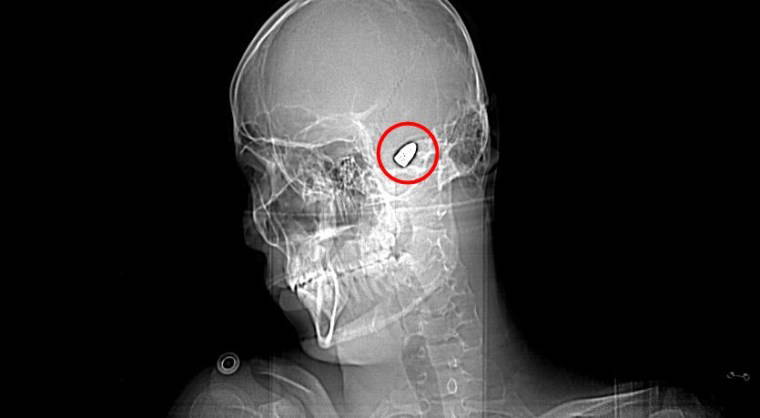

Çevredekilerin hastaneye götürdüğü Yusuf’un çekilen röntgeninde, başında mermi çekirdeği olduğu tespit edildi. 4 gün yoğun bakım, 4 gün de serviste tedavi gören Yusuf’un başındaki mermi için doktorlar, riskli bölgede olduğu gerekçesiyle müdahale etmedi.

Düzenli olarak kontrol edilen Yusuf’ta konuşma güçlüğü ve sağ el ve parmaklarında zayıflık belirtileri ortaya çıkınca fizik tedavi süreci başladı.